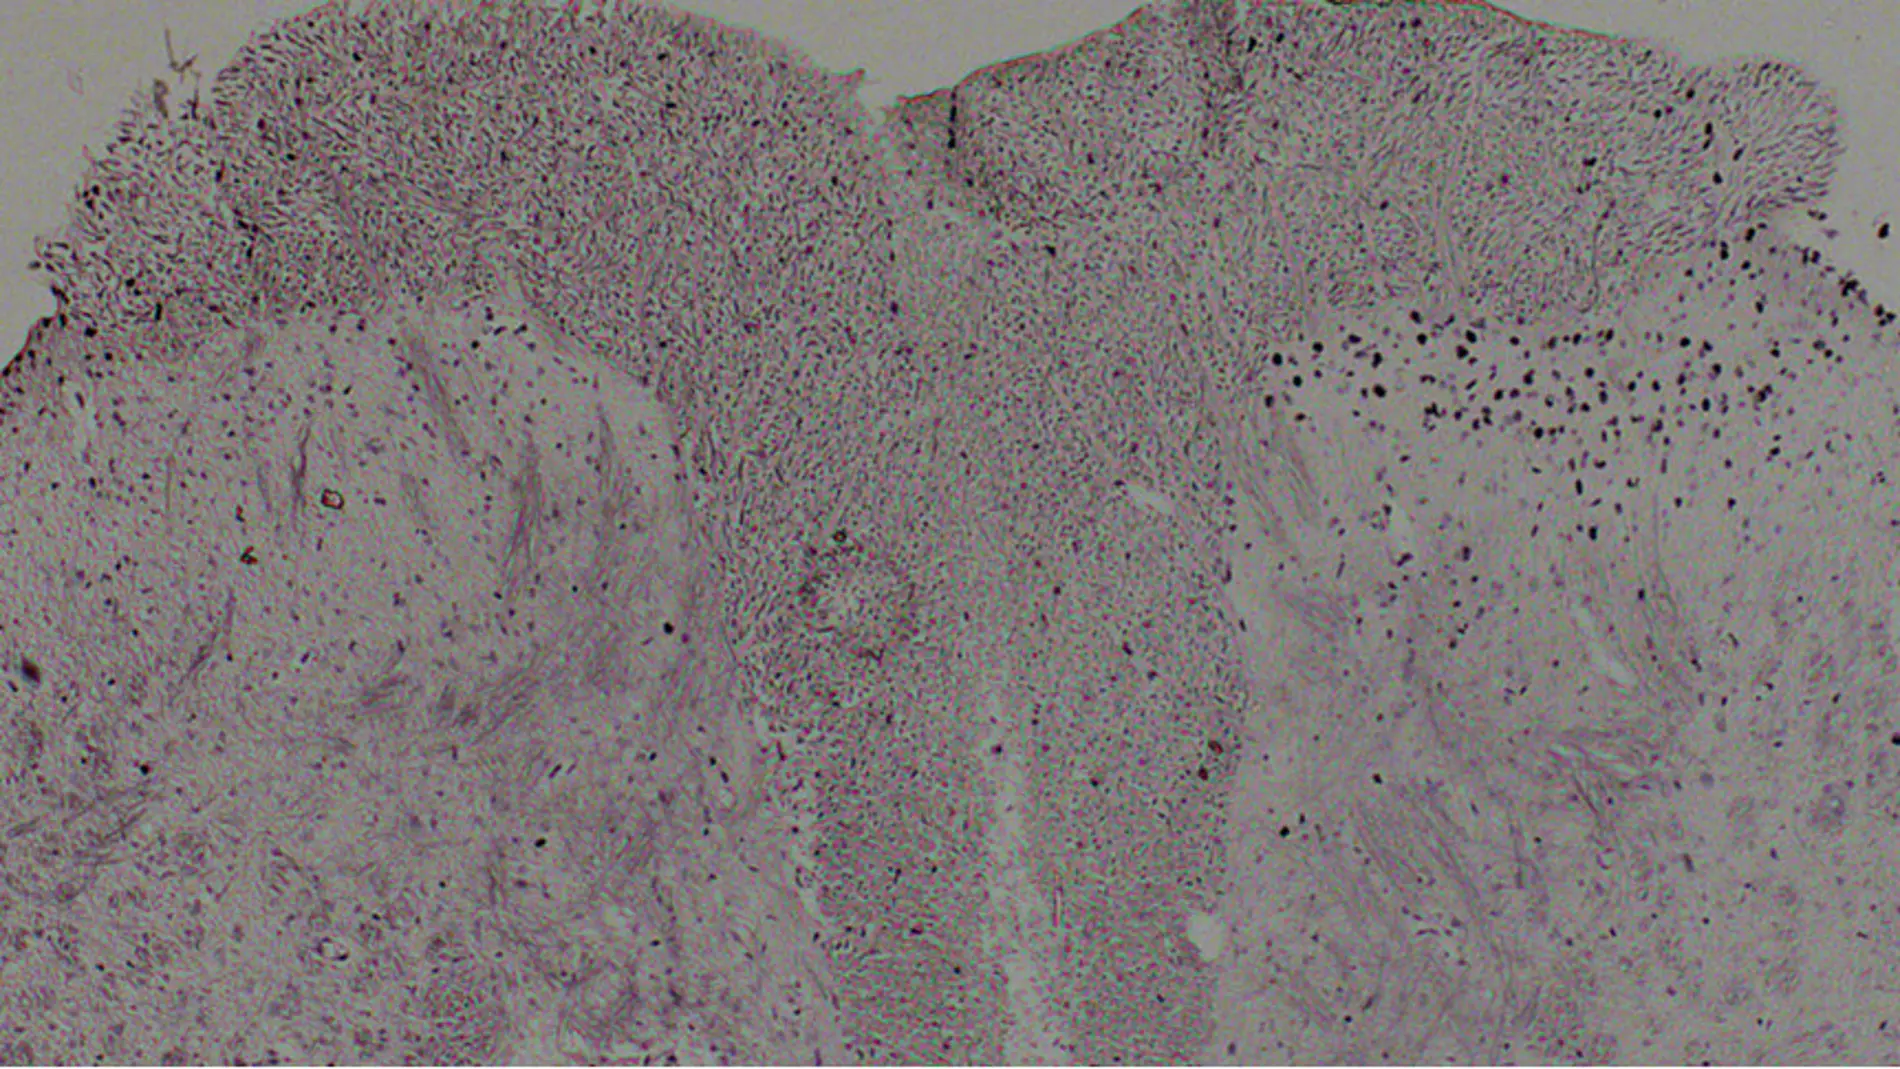

El desarrollo y la persistencia del dolor dependen de cambios plásticos en las neuronas que procesan la información sobre los estímulos nocivos, que son las del cuerpo dorsal de la médula espinal.

Esos cambios plásticos en gran parte están regulados por mecanismos epigenéticos –es decir, cambios químicos que alteran la expresión de los genes, pero no su secuencia– como modificaciones postraduccionales de las histonas.

Técnicamente, el equipo en el que trabaja el experto español ha demostrado en ratones que una población de neuronas superficiales de la médula espinal controla un marcador epigenético conocido como pS10H3.

“Hemos observado este efecto después de utilizar diferentes modelos animales de dolor: inducción de quemaduras, aplicación de capsaicina o estimulación eléctrica del nervio”, apunta Torres Pérez.